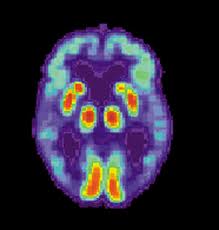

I came across the linked article above and found this Alzheimer’s development quite interesting. The WebMD article cites that “differences in plaque-forming structures in the brains of Alzheimer’s patients may offer clues to why the disease can progress more rapidly or be less severe in some people.”

After implanting proteins into two deceased female Alzheimer’s patients, scientists found that the proteins assembled into different molecular structures. Not only does this help scientists verify two structural varieties of Alzheimer’s, it could also lead to diagnosing and treating afflicted patients at earlier stages. The hope is that this information will give insight into the severity of someone’s condition.

Nothing is what it seems in a brain infected with Alzheimer’s. The fact that the same injections of protein could transfigure into different molecular structures only makes sense for no one symptom or test can fully confirm the presence of the disease in the brain. Rather, it is a well-established group of symptoms that when observed in conjunction confirms the condition. An Alzheimer’s patient exhibits impaired memory as well as problems in at least one other area of thinking or functioning, including cognitive symptoms, language problems, changes in personality, problems interacting in social environments, and physical behavior. The patient may experience difficulty in recalling previously known information, learning new information, recognizing spaces or faces, processing language, speaking in coherent sentences, and deciphering meaning. Each patient yields a different combination of results, a fact I can corroborate from personal experience.